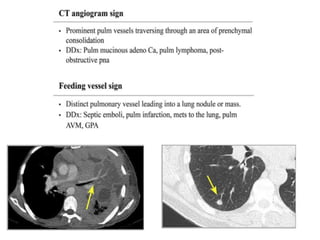

VASCULAR SIGN

• FEEDING VESSEL SIGN

• CT ANGIOGRAM SIGN